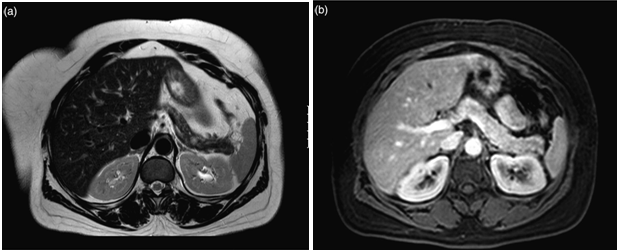

CT scan has many advantages since it can be easily performed, is non-invasive and the images are easily interpretable for the surgeon. Insulinoma typically appear as well-defined, rounded, homogeneously masses of the pancreas. Because the majority of insulinoma are usually smaller than 2cm, dynamic CT scan should be performed; the sensitivity of the dynamic CT scan in the detection of insulinoma ranges from 30% to 66%. Dual-phase contrast spiral CT scan is more sensitive than other noninvasive imaging studies. In a group of seven patients with tumors that were biochemically proven but not previously located by ultrasonography, CT scan, or magnetic resonance imaging, six of seven tumors ranging from 6 to 18 mm were detected by dual-phase spiral CT scan. Atypical CT scan imaging of insulinoma includes hypoattenuating masses on enhanced CT or intra-arterial dynamic CT, cystic masses, and calcified masses (Figure 1–3).26–30

Figure 1 Insulinoma in an 87-year-old man with intractable hypoglycemia. Dual phase CT scan through the pancreas demonstrates a subtle, well-defined 1-cm enhancing lesion (arrow) in the pancreatic neck. A small cyst is also seen. A well-differentiated 1.2-cm ICT was completely excised at surgery. Histologic stains were positive for insulin. The hypoglycemia resolved after surgery. 23

Figure 2 Pancreatic insulinoma. Axial contrast-enhanced CT scan obtained during the arterial phase shows a homogeneous enhancing lesion (black arrow) in the uncinate process of the pancreas, just posterior to the superior mesenteric vein (white arrow). 24

Figure 3 Insulinoma in 24-year-old woman who presented with hypoglycemia. Because of clinical likelihood of insulinoma, noncontract CT scan was initially obtained. Subtle 2.0 × 3.0cm area of high attenuation in pancreas (arrow) is found to represent calcified insulinoma at surgical pathology. 25